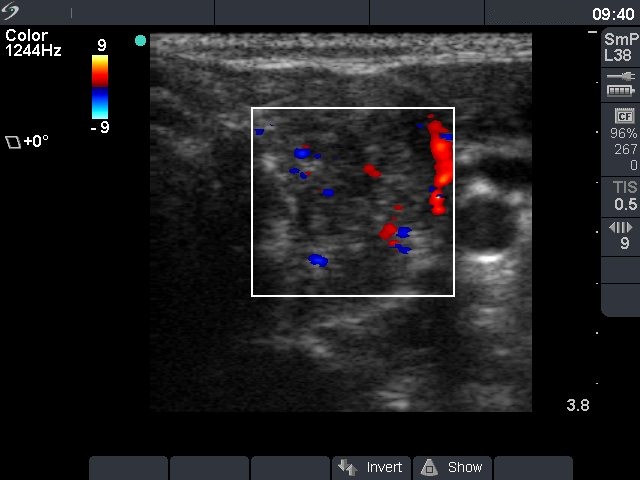

Ultrasonography: the thyroids were hypoechogenic and inhomogeneous. There was a more inhomogeneous nodule in the upper part of left lobe. The nodule contained microcalcifications and presented intranodular blood flow.

Comment: it is worth comparing the insignificant discrete lesions detected in the right thyroid and the nodule in the left lobe on the video. Note the difference in echogenicity and vascularization.